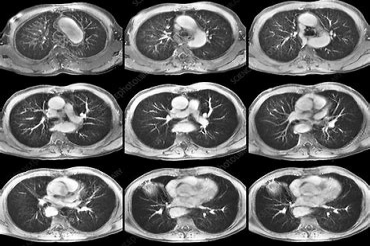

心脏的三大主要血管被称为LDA、RCA和CIR,它们可以为心脏提供足够的血液和营养,使心脏保持正常的功能循环。

前降支和回旋支一般分布在心脏左侧,右冠状动脉则在右侧。如果三支血管中有一支的狭窄程度超过50%,就可以诊断出冠心病。

心脏血管可以为心脏提供足够的血液和营养,使心脏保持正常的功能循环。一旦心脏三大血管堵塞,心肌的血液供应就会受到严重影响,容易导致冠心病和心肌梗死,从而危及患者的生命安全。